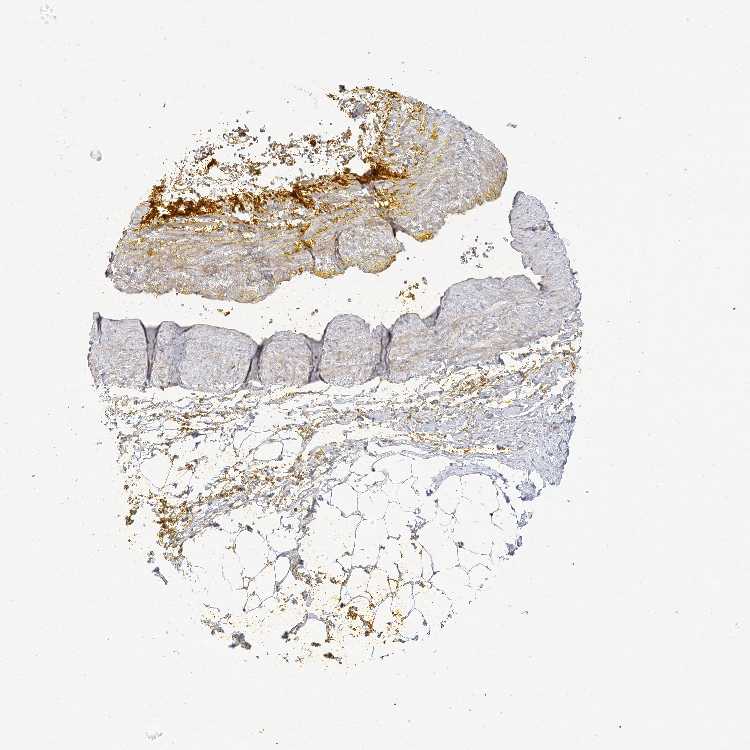

SOFT TISSUE 1 - Antibody stainingi

Antibody staining in the annotated cell types in the current human tissue is reported as not detected, low, medium, or high, based on conventional immunohistochemistry profiling in selected tissues. This score is based on the combination of the staining intensity and fraction of stained cells.

Each image is clickable and will lead to virtual microscopy that enables deeper exploration of all samples and also displays staining intensity scores, fraction scores and subcellular localization as well as patient and tissue information for each sample.

Antibody HPA037914

Chondrocytes Medium

Fibroblasts Low

SOFT TISSUE 2 - Antibody stainingi

Chondrocytes Low

Peripheral nerve Not detected